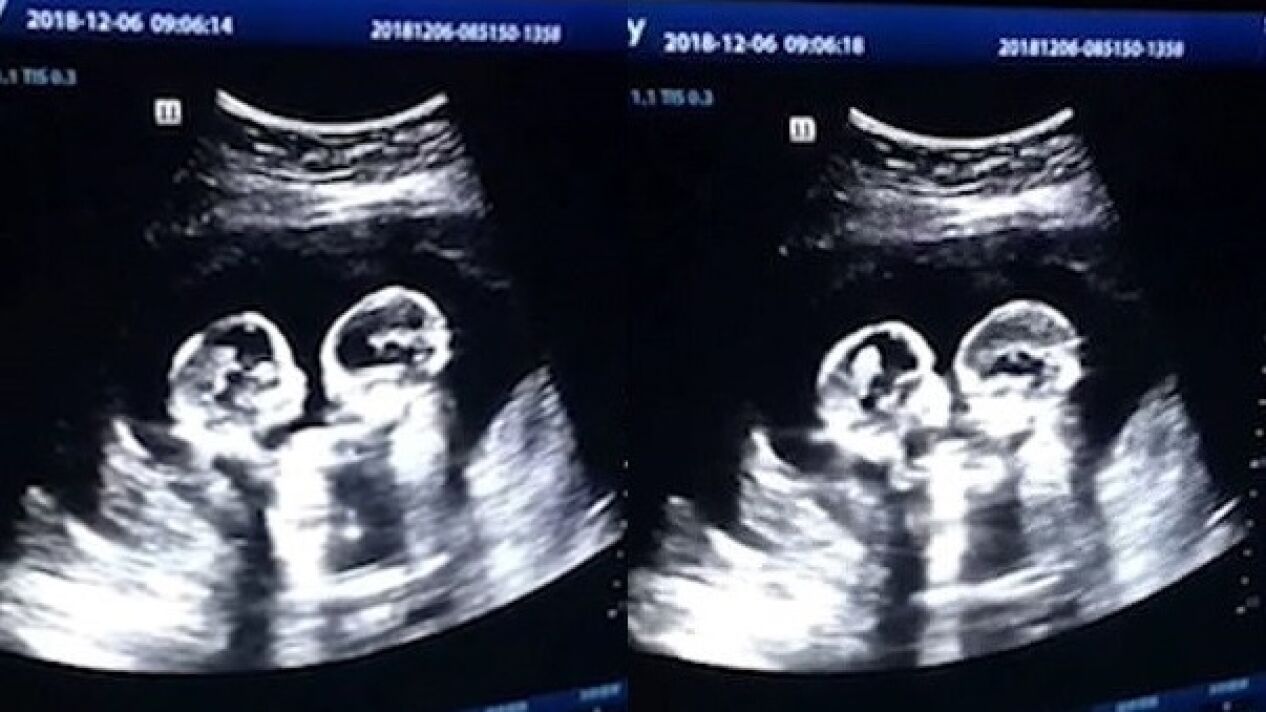

COMPARTÍAN EL MISMO SACO AMNIÓTICO

Una ecografía capta a dos gemelas 'peleandose' dentro del útero de su madre

Las hermanas, que han nacido sanas y salvas, se 'golpeaban' durante las revisiones ginecológicas de su madre.

En Yinchuan, China, dos gemelas fueron grabadas el pasado diciembre 'peleándose' dentro del útero durante una revisión en el cuarto mes de gestación, según ha recogido el 'China Daily'.

La ecografía reveló cómo las dos hermanas comenzaban a darse 'patadas' y 'golpes' en el interior de la barriga de su madre.